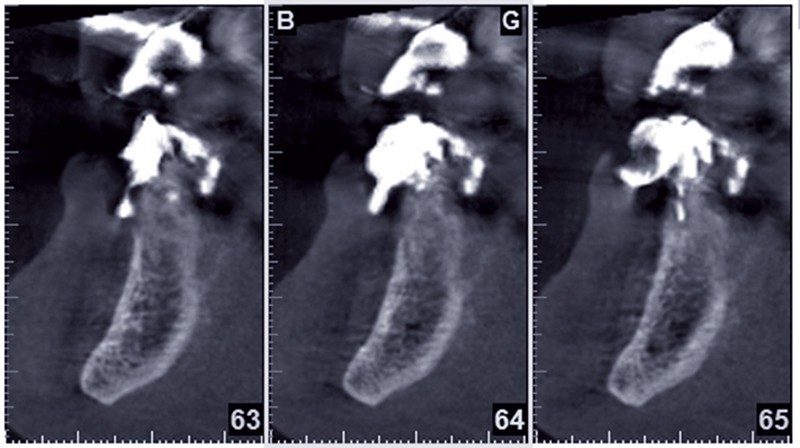

Cette ostéointégration est confirmée par le Cone Beam(fig. 4a et b).

Le suivi à 6 ans de ce cas confirme donc les résultats prometteurs observés à court terme ainsi que les premières publications cliniques et fondamentales [4, 9]. Dans les chirurgies de préservation de crête, NovaBone® apparaît être un substitut fiable puisqu’à la réouverture à 4 mois, on note une reconstitution quasi ad integrum du volume osseux. De plus, le remplacement quasi complet des particules de NovaBone® par un os néoformé bien vascularisé permet la pose et le blocage des implants dans les sites [7].